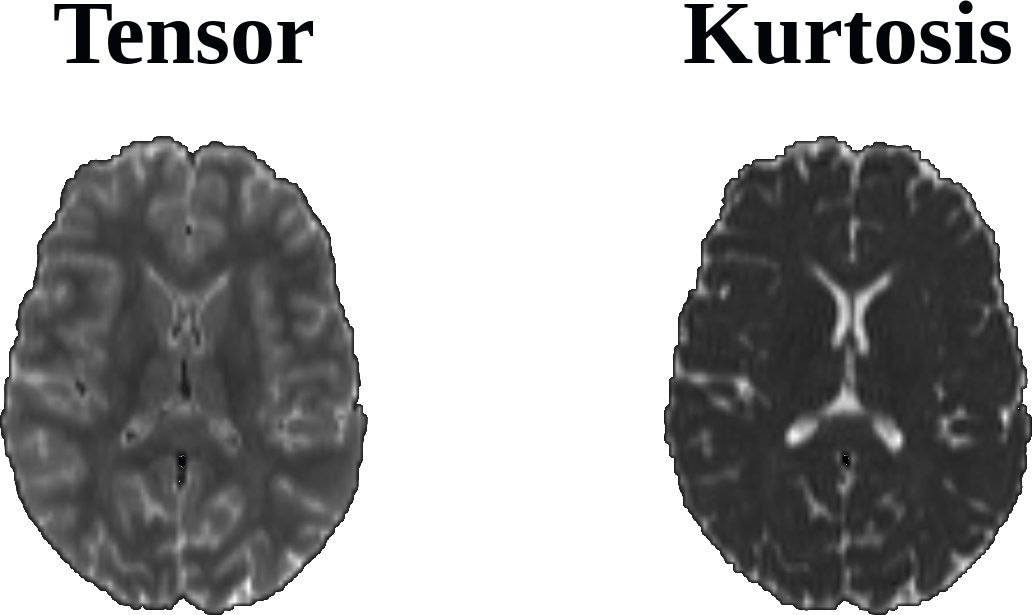

Attached is a single-subject MD map, calculated via the Tensor and Kurtosis models:

This behavior is somewhat unexpected, especially due to the same voxels being given high MD values when computed via DIPY's ReconstDkiFlow for reconstructing the tensor using the kurtosis model.